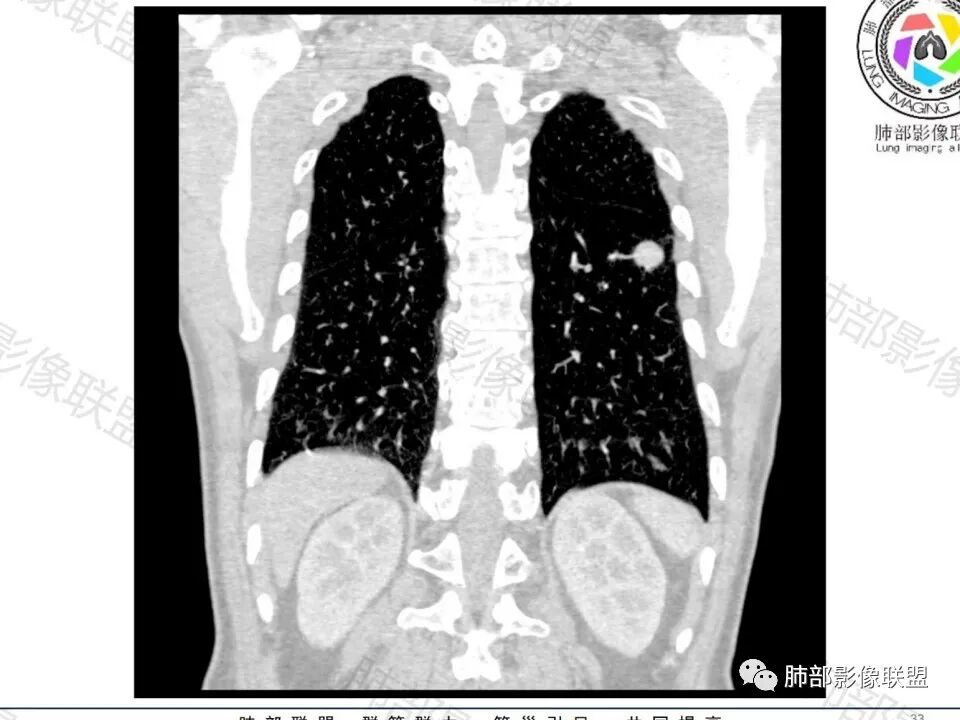

左下肺、右中肺均有结节,左下肺病灶比较鼓,边缘有晕,血管弯,持续性强化,考虑腺癌可能,鉴别两处病灶如果一元论,肉芽肿炎 (隐球)

图做的真漂亮!老年男性,双肺多发结节,最大者位于左肺下叶胸膜下,周围有晕,晕中毛刺,边缘有一囊腔,胸膜牵拉,持续强化,考虑隐球,鉴别腺癌。

左肺下叶胸膜下类圆形结节,边缘光滑,周围有晕,晕中有毛刺,周围可见小卫星灶,相邻胸膜增厚,血管进入,右肺中叶可见小结节影,考虑炎性肉芽肿,隐球菌。鉴别腺癌。

晨读:左肺下叶胸膜下实性小结节,边缘可见模糊晕及毛刺,轻度收缩,与支气管关系不清,近端与血管束相连,内见小空泡,平扫密度均匀,均匀强化。远近可见多个小结节。考虑炎性肉芽肿,隐球菌病,鉴别结核、腺癌。

多发类似结节

1、炎性结节,多发,类似,晕,隐球菌?

2、恶性:多发:转移瘤?肺癌并多发转移瘤?